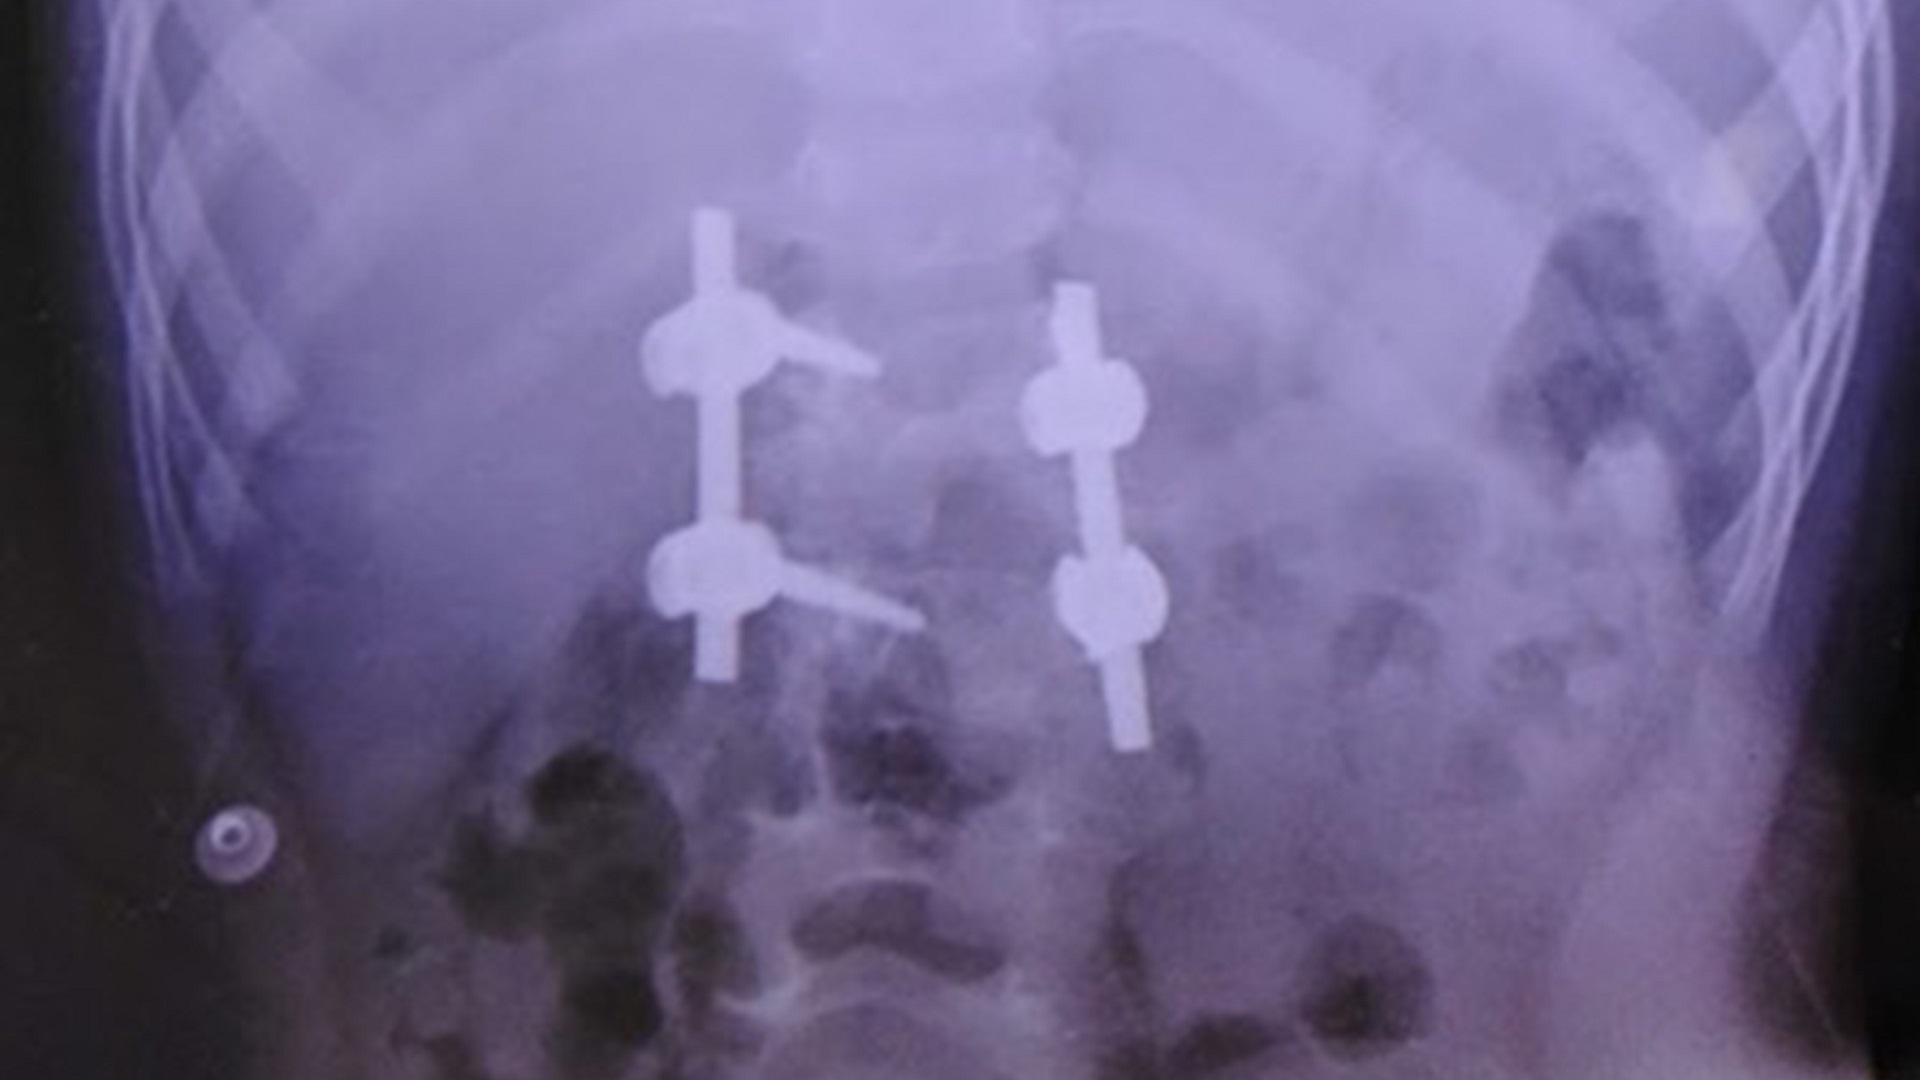

Corrigen malformación de columna a niña de 4 años en el IMSS - implantes-pediatricos

Implantes pediátricos. Foto de IMSS

En febrero pasado, los especialistas del IMSS retiraron la vértebra de Fátima con mala formación y le colocaron implantes pediátricos para nivelarla.